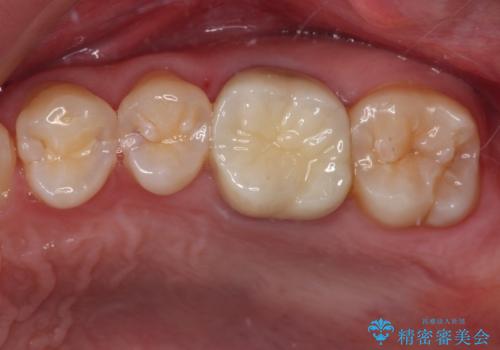

- 以前他院にて、保険診療で治療した金属のブリッジをやり替え希望の患者様です。

奥歯であっても、大きく笑うと金属色が目立ちます。

金属ブリッジを除去し、虫歯を完全に除去し、形を整え、

精度の高いシリコーン材料にて型どりをしました。

精度の高いブリッジなので、しみるなどの症状もなく経過も良好です。